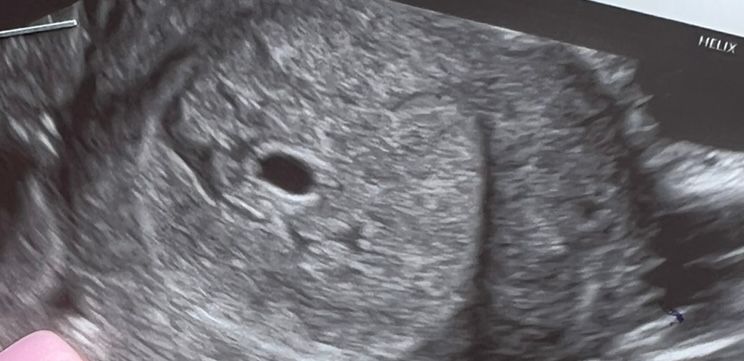

Мама котят, вроде бы нет. Но я увидела на узи что рядом с ПЯ как будто жидкость, доктор сказала это формируется плацента. Вот можете увидеть с левой стороны от ПЯ